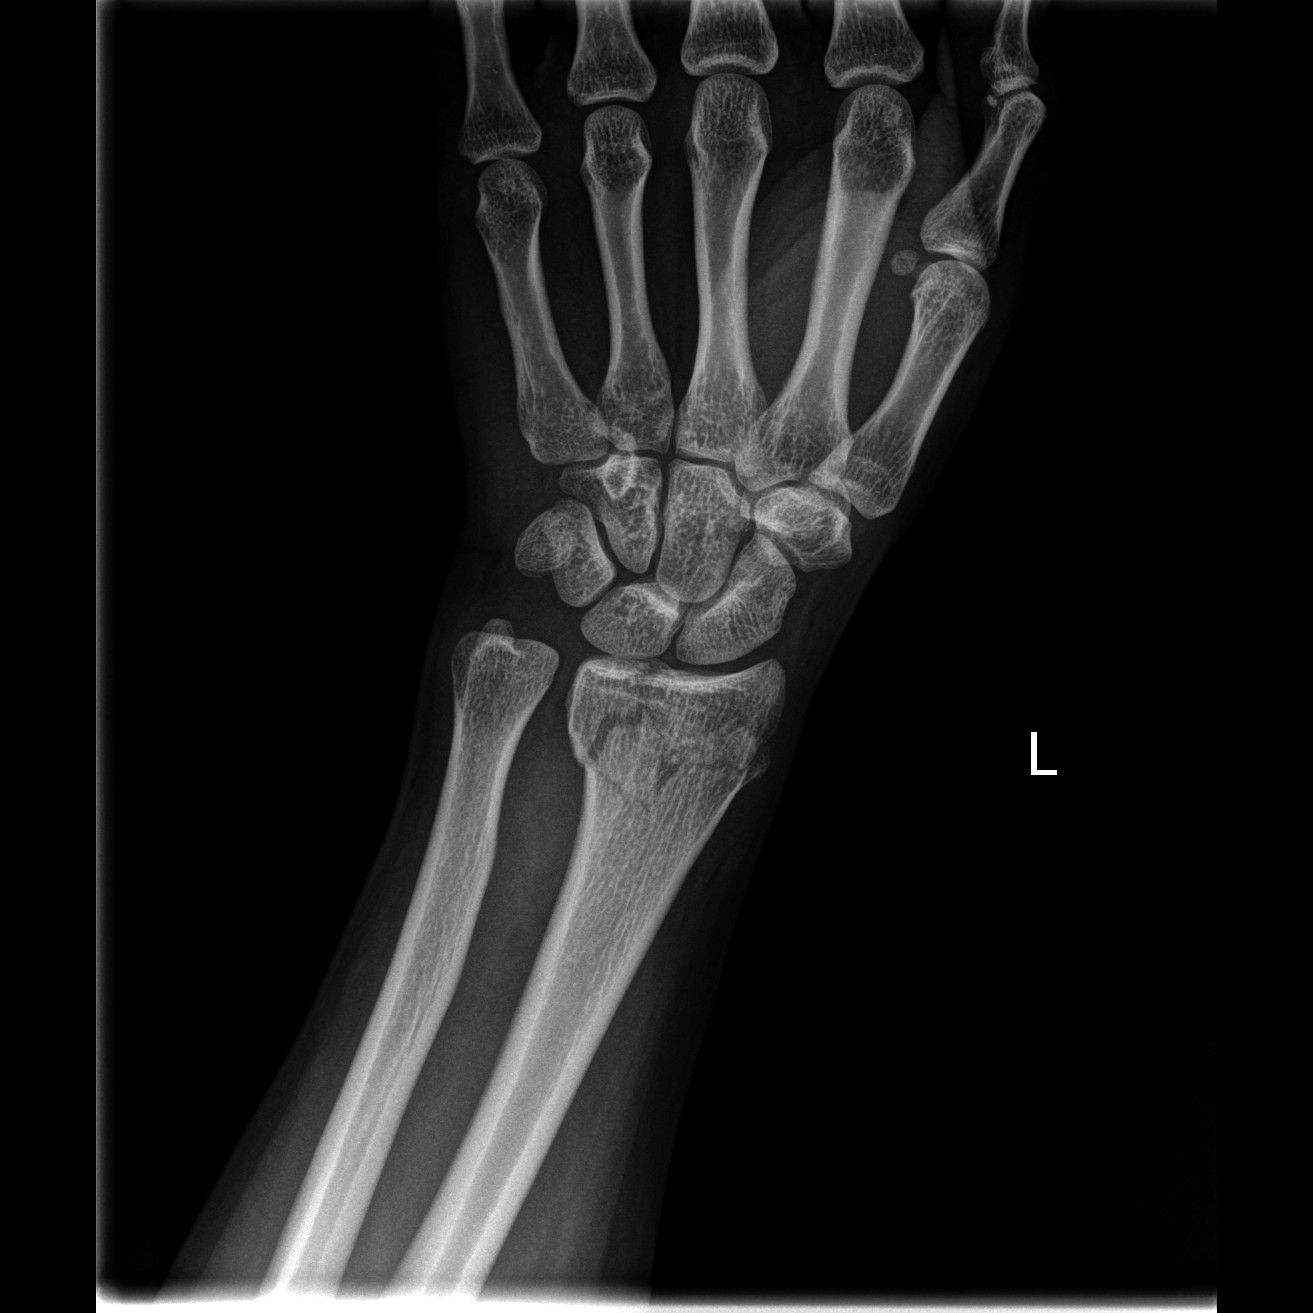

前臂双骨折,约占骨折总数的11.2%,多见于青少年。